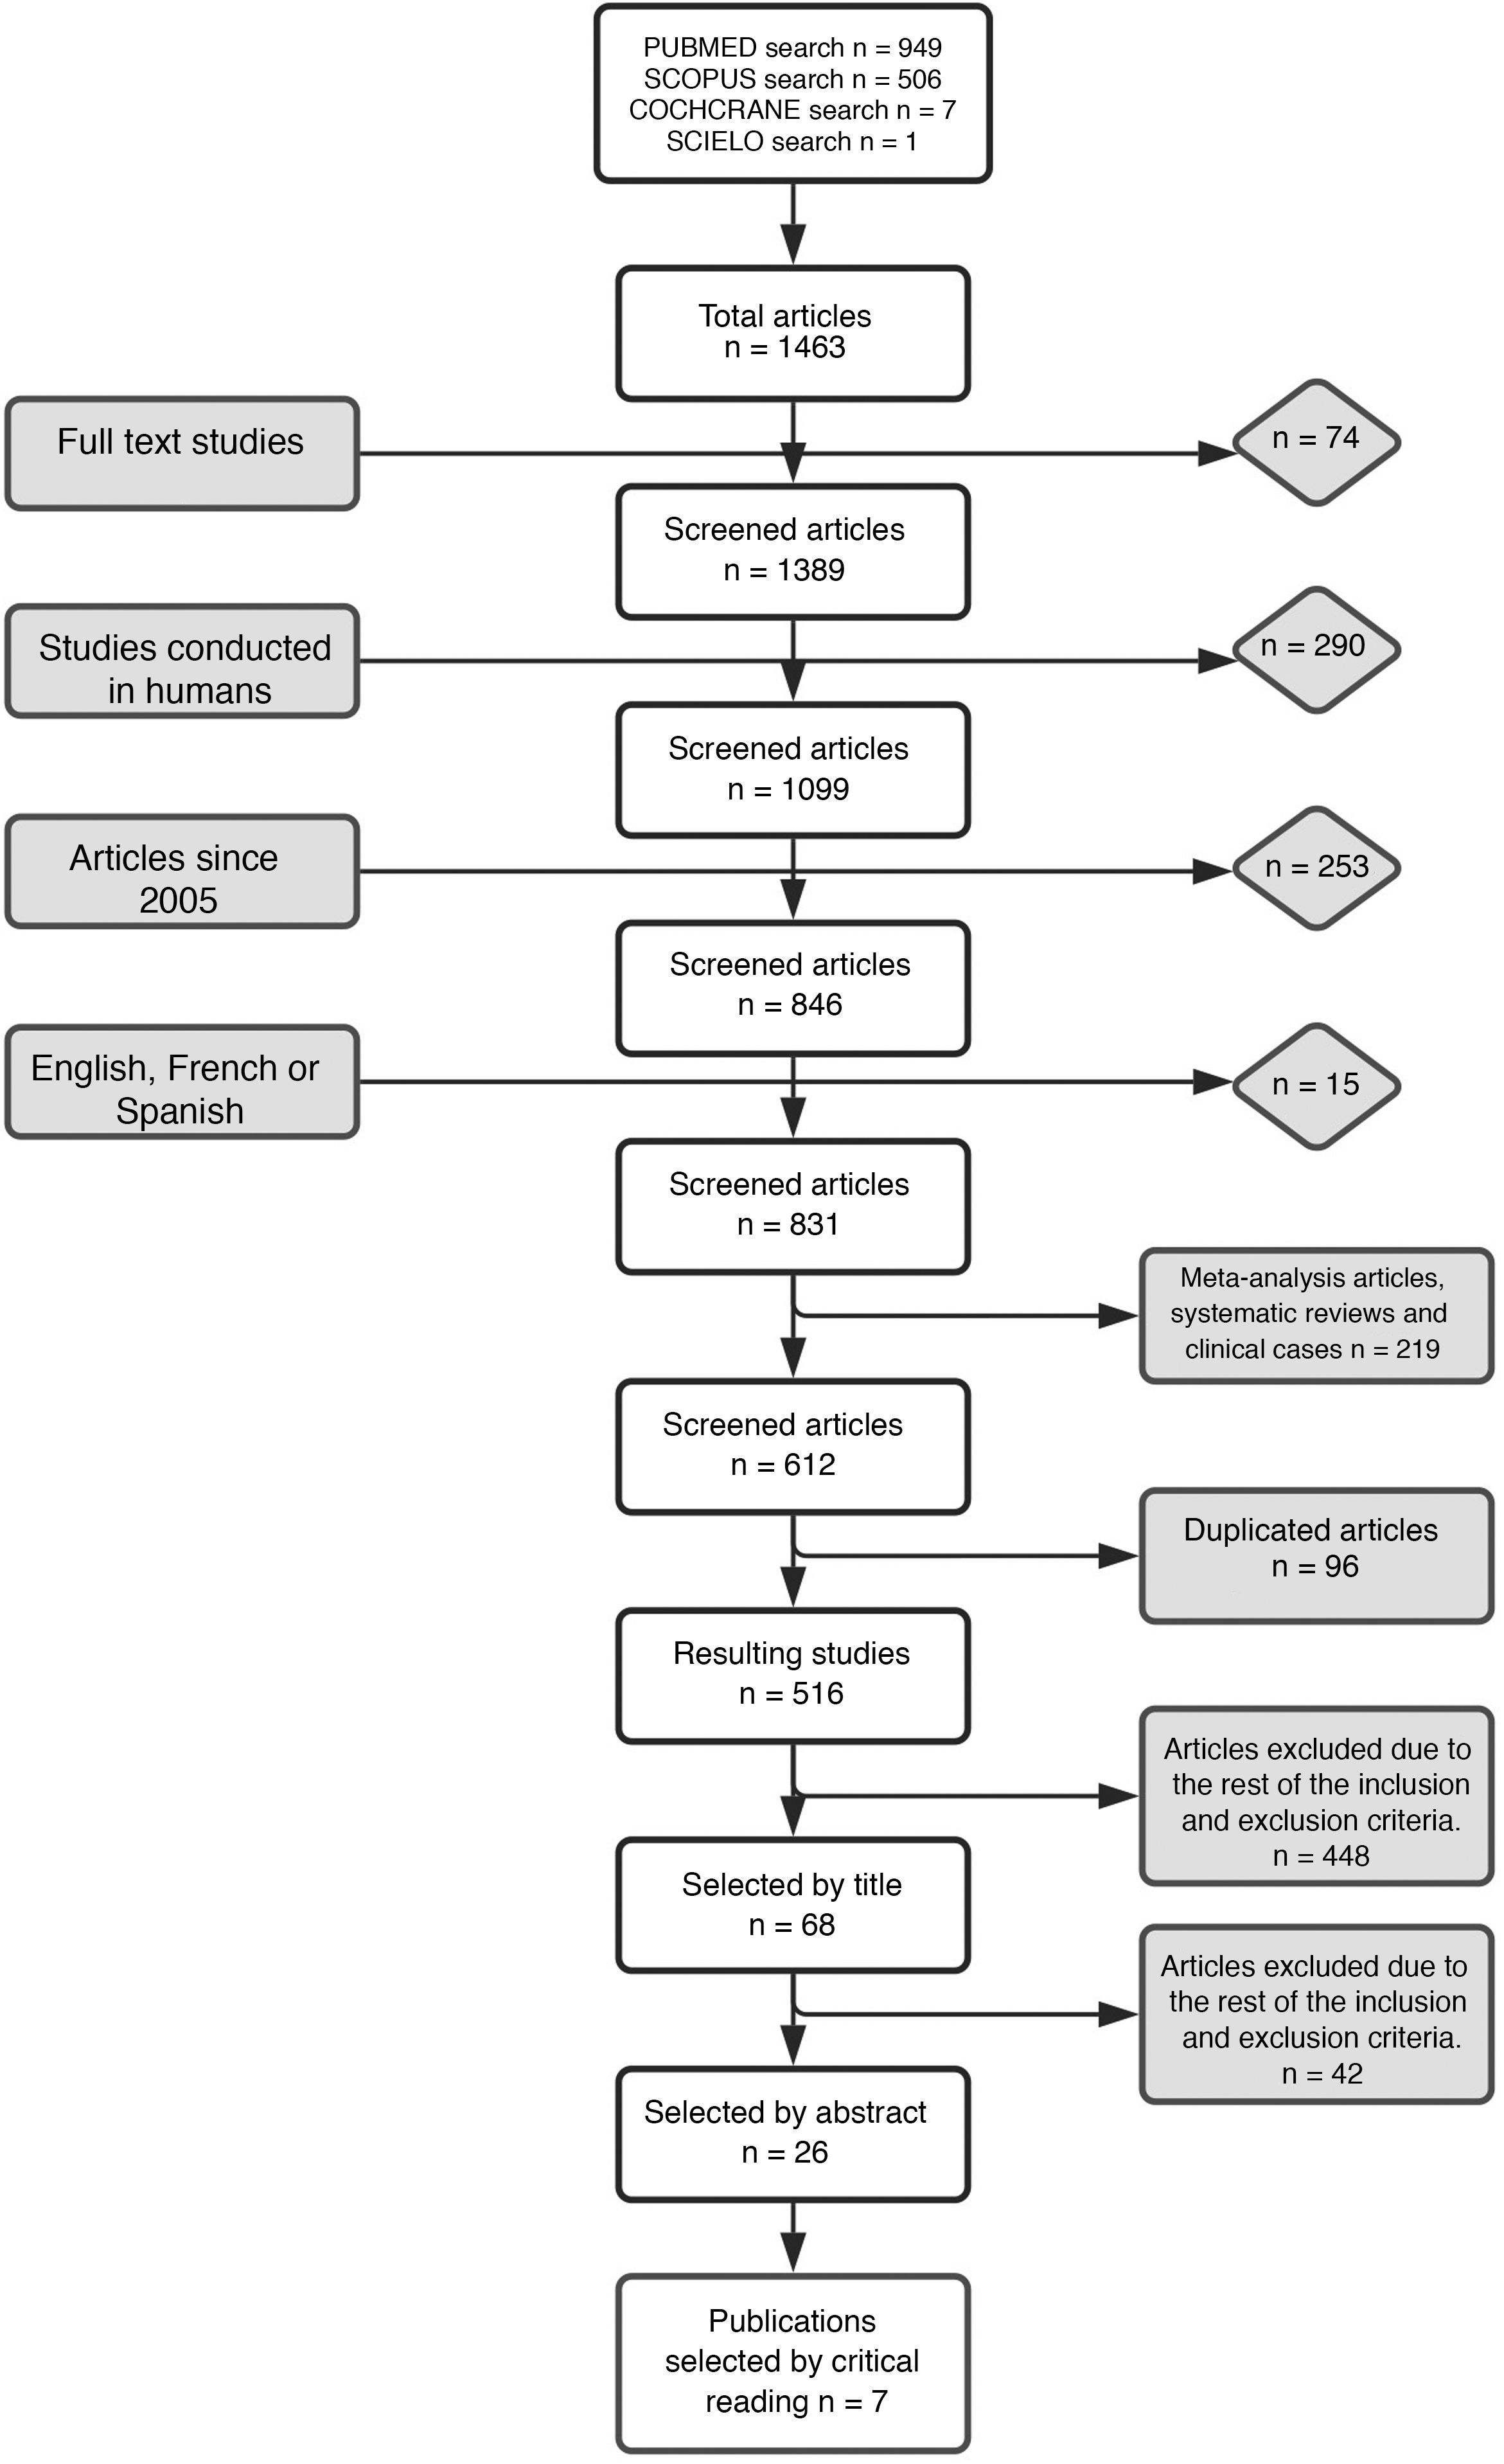

Material and methodWe realize a systematic analysis and identify important factors for long survivor patients. We also show an own case with more of 20 years of survival. We make a new pathological study of the old paraffin block of this patient.

ResultsThe most important variable associated with long-survival between all multivariant studies is the age. When we try to find genetic and molecular alterations in glioblastoma associated with prolongated survival, the MGMT promoter methylation play the most important role. We find a correct diagnosis in the current analysis of our patient’s sample with very long survival.

Material y métodosSe realiza un análisis sistemático de la literatura identificando los factores que pueden influir en los pacientes de larga supervivencia. Se identifica un caso en nuestro medio de más de 20 años de supervivencia realizándose un análisis actual del bloque de parafina que se conservaba del paciente.

ResultadosLa variable que más se asocia a la larga supervivencia en todos los análisis multivariantes es la edad, aunque, cuando se analiza las características genéticas y moleculares de los tumores, parecen existir otras variables como la metilación del promotor MGMT que juegan un papel muy importante. El análisis anatomo-patológico actual de la muestra comprueba la certeza del diagnóstico en nuestro paciente de muy larga supervivencia.